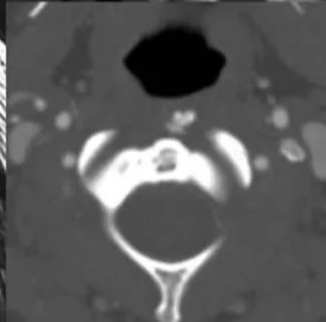

患者做完CT回来说,做CT的途中都痛哭了。颈部CT结果如下:枢椎左前方软组织钙化灶。

枢椎左前方软组织钙化灶

颈椎CT提示:枢椎左前方软组织钙化灶。

明确诊断主要通过典型的临床表现结合影像学方法,颈椎CT是关键。颈长肌钙化性肌腱炎特异性的影像表现是C1-4椎体前缘软组织肿胀和积液与C1椎体前弓下方不规则钙化沉着共存。

C1椎体前弓下方不规则钙化沉着

CT的高分辨率能够明确肌腱内的钙化,能够明确是钙化而不是其他骨骼来源的高密度影。钙化一般位于寰椎前弓的下方和枢椎齿状突的前方,少部分可位于下颈椎前侧。CT有助于明确椎体前积液的存在和排除其他病理表现,如骨折或脓肿。MRI对诊断不是必须,但有时可帮助确定软组织异常,排除咽后脓肿,脊椎炎或肿瘤。MRI检查T2加权在椎前可见局限性的裂隙样区域,大多位于C1-4水平,呈高信号改变,这反应是由于炎症引起的积液。T2加权、脂肪抑制序列和T1加权对鉴别积液和脂肪组织、含脂肪的骨髓以及咽后感染、脊椎炎有重要作用。MRI检查在钙化检查方面存在不足,T2加权呈低信号。